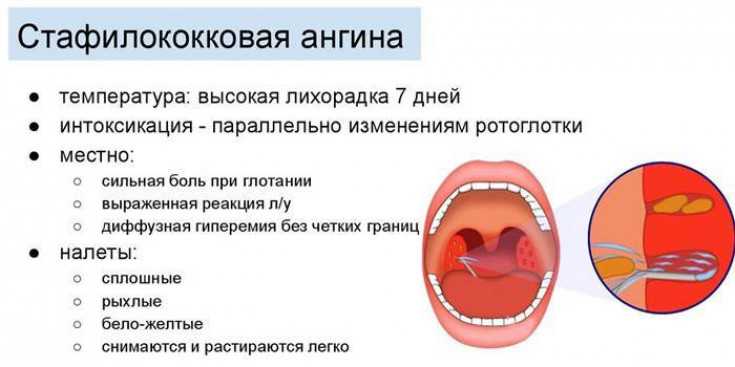

Виновниками гнойной ангины у детей наиболее часто бывают патогенные бактерии: стафилококки, пневмококки, диплококки, стрептококки и прочие. Вся эта микрофлора всегда присутствует в верхних дыхательных путях человека и, если в норме, не опасна для здоровья.

При проведении микробиологического исследования посева с поверхности миндалин выявляют следующих возбудителей тонзиллита:

- 30-40% бета-гемолитический стрептококк группы А;

- 28-30% стрептококки группы С и G;

- 20-25% стафилококки;

- 5-22% иные микроорганизмы: нейссерия, микоплазма, пневмококк и др.

Наиболее часто бактериальная или гнойная ангина у детей вызывается бета-гемолитическим стрептококком группы А. Причина заключается, прежде всего, в его строении: они несут капсулы (М-белок) для адгезии к слизистой оболочке миндалин. Эти микроорганизмы устойчивы к фагоцитозу и выделяют различные экзотоксины. Последние приводят к выработке антител, которые перекрестно действуют еще и на сердечную мышцу, ткань сосудов, суставов и почечную паренхиму.

Если организм ослаблен, бактерии могут проникнуть в миндалины и начать размножаться, вызывая патологические изменения в лимфоидной ткани. Это приводит к развитию катарального воспаления, которое может прогрессировать в гнойный процесс. В результате возникает фолликулярная ангина, которая характеризуется наличием гнойных изменений в фолликулах. При осмотре зева видна “звездная” картина, где на гиперемированном фоне можно увидеть точечные скопления гноя белого или беловато-желтого цвета. Процесс продолжается, гнойные фолликулы вскрываются, гной вытекает и проникает в лакуны, где образуется новый очаг воспаления, что приводит к лакунарной ангине.

Разделение на фолликулярную и лакунарную формы условное, поскольку часто обе стадии диагностируются одновременно. По клиническому течению они практически не отличаются, разница заключается только в фарингоскопической картине. При осмотре зева видны лакуны, заполненные гноем, которые имеют неправильную форму и напоминают поверхность “гриба мухомора”

Важно отметить, что процесс никогда не выходит за пределы небных дужек и локализуется только на миндалинах